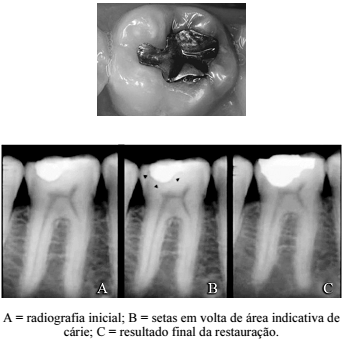

Paciente do sexo masculino, com quarenta e dois anos de idade, procurou atendimento odontológico porque sentia incômodo em um dente inferior, do lado esquerdo, ao ingerir líquidos gelados. Após ter sido submetido a exame radiográfico, constatou-se pelas imagens radiográficas a presença de cárie no elemento 36, com espessura radiográfica normal do espaço do ligamento periodontal, além de ausência de esclerose óssea periapical e ausência de sintomatologia dolorosa. As respostas foram consideradas normais para os testes térmicos de sensibilidade pulpar (frio e calor). A foto a seguir mostra a condição clínica inicial e as imagens radiográficas mostram a sequência do caso clínico com a substituição da restauração em amálgama.

Considerando o caso clínico 24A1AAA e as imagens precedentes, julgue o item a seguir.